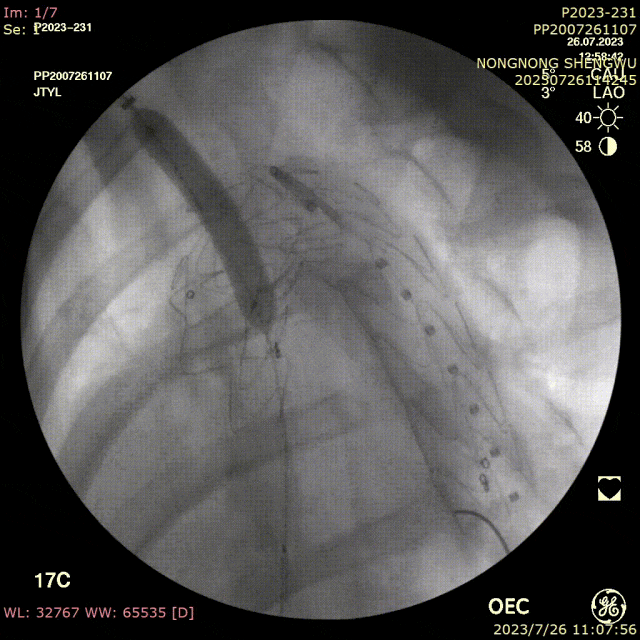

手术过程:

全麻下双上肢穿刺,右股动脉切开,左上肢路径造影,右上肢进保护性导丝,对支架预开窗后植入升主,因破口较大,支架近端掉入破口,远端扭转遮蔽左颈总动脉及头臂干,窗口对破口,再次植入一枚38-80支架,封住近端破口后,以8*60支架开放右侧头臂干,6*10人工血管行右锁骨下-左颈总搭桥,取颈前静脉行左椎动脉-人工血管搭桥,之后造影,头臂动脉均通常,术后约2小时患者清醒。